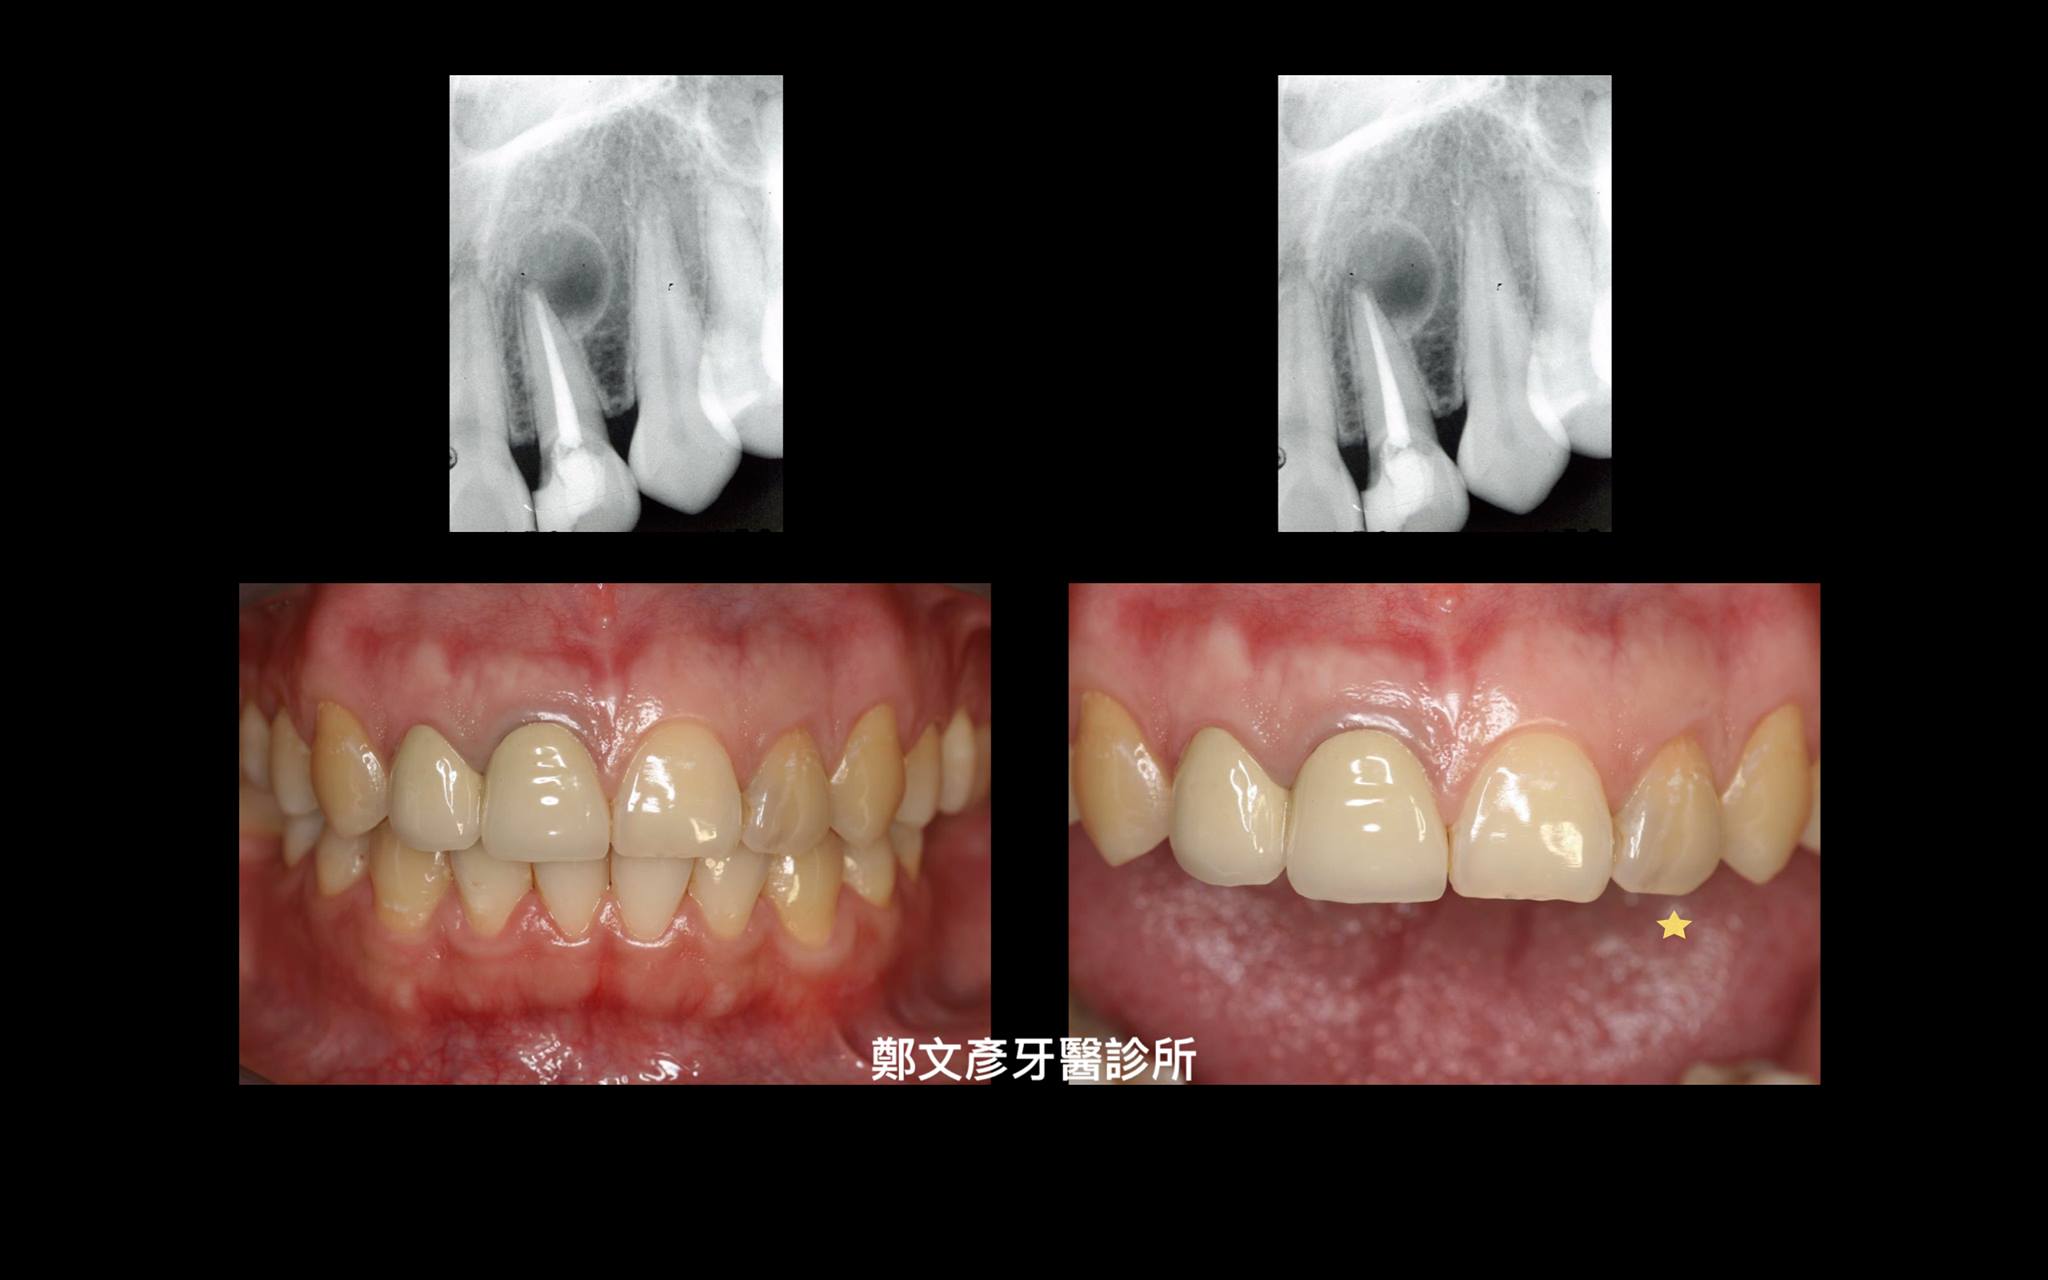

前牙植牙美學及軟組織轉移

植牙美學

Role of granulation tissue in socket preservation